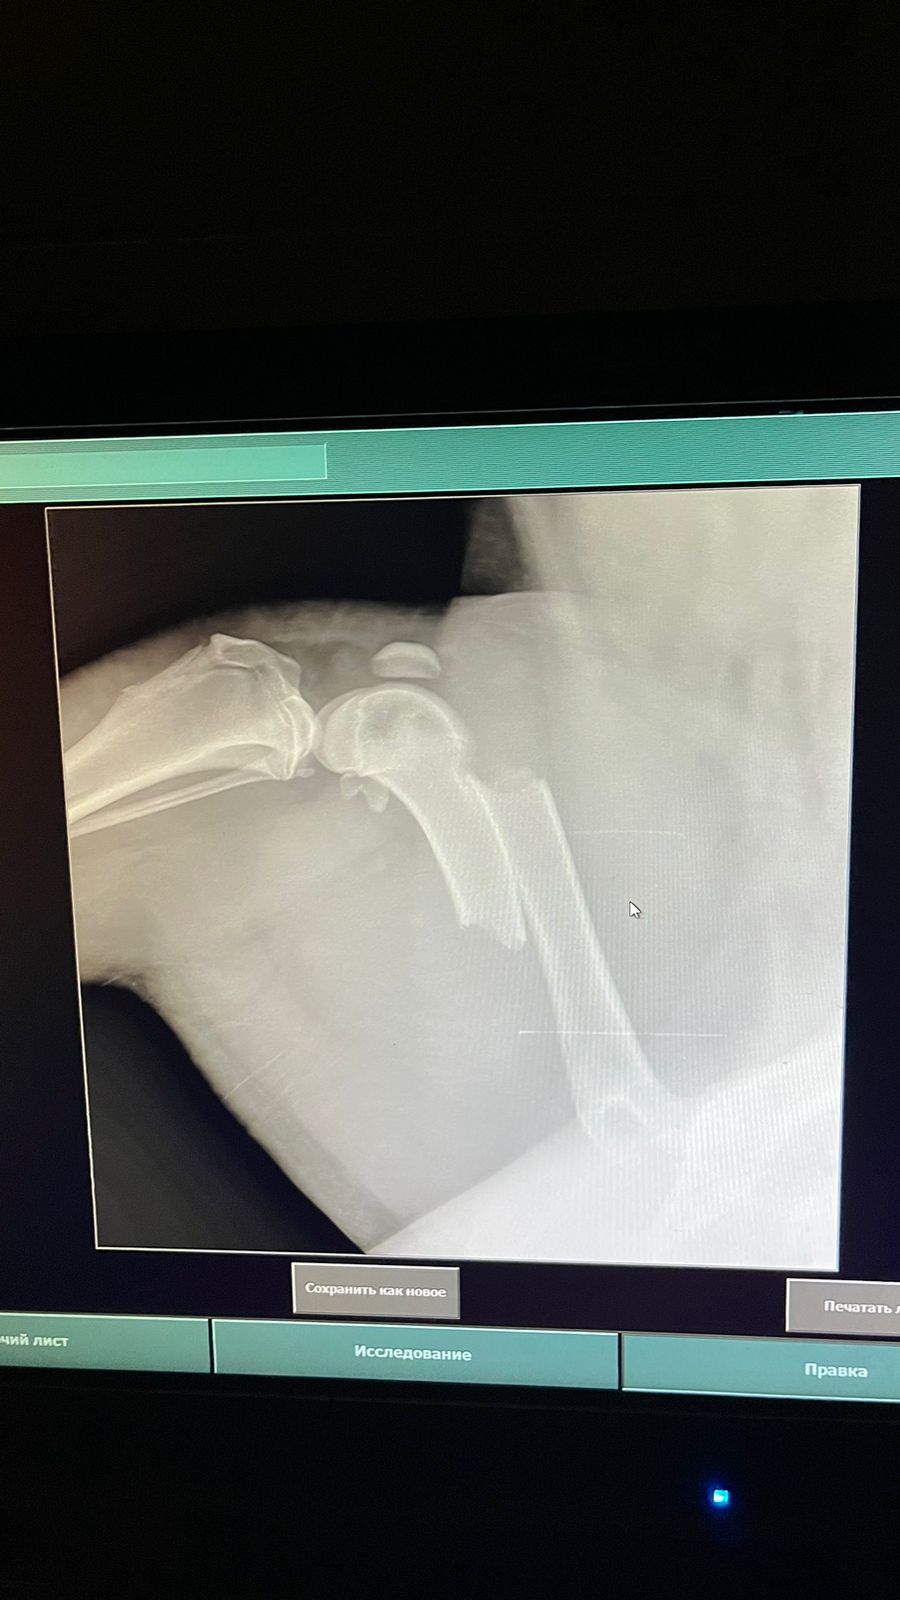

Волонтёр привела молодую суку ризена со сломанной лапой в клинику к Насте pani Stasi. Вроде перелом не сильно свежий.

Ногу будет хирург смотреть и может в ближайшее время прооперируют.

Её забрала заводчица. И что-то там у них случилось, то ли лошадь понесла, то ли что, в общем, собака перепрыгивала через телегу и сломала лапу. У заводчицы тоже ключица сломана, может ещё что-то.

Ветеринар позвонила знакомому волонтёру, говорит, чего усыплять, я её соберу, рентген только надо.

Операцию сделали, собрали лапу на две пластины. Выписка попозже будет.

Да, задняя правая сломана.